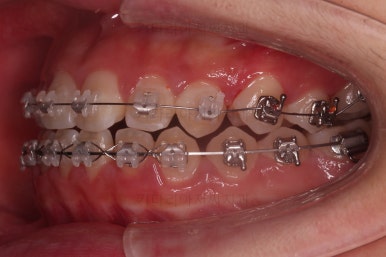

악궁확장 이 후 브라켓을 부착합니다.

이번 환자분이 선택하신 장치는 엠파워 클리어라고 하는 자가결찰 세라믹 장치인데요.

그런데 이번 치료의 핵심은 따로 있습니다.

바로 "재발" 인데요. 원래대로 돌아가려는 경향, 이번 환자분은 다시 틈새가 생기려는 경향인데요.

아주 다양한 틈새의 원인이 있으나 이번 환자분은 호흡기, 호흡기에서 비롯된 혀의 문제가 가장 큰 이유였습니다.

혀를 잡아야 한다.

혀는 사실상 성장기 때 구강구조에 매우 영향을 많이 미칩니다.

이번 환자분은 틈새가 만들어지는 방향으로 혀가 힘을 주었던 상황이었고요.

혀 내밀기라고 하죠.

그래서 교정 중에도 혀를 인지하고 연습할 수 있도록 불편한 장치를 구성했고요.

교정치료 후에도 특별한 장치를 제작해 드릴 생각입니다.

틈새가 벌어지더라도 뒤쪽에 벌어지라고 앞니쪽은 유지철사를 부착하고요.

동래교정치과 키다리아저씨치과만의 독특한 디자인의 유지장치를 추가로 드리게 됩니다.

전후 사진을 비교해 볼게요.

악궁확장을 통해 위아래 악궁의 크기 조화를 맞췄고, 틈새도 모았으며 교합도 적절히 마무리를 했습니다.

향후 유지관리가 다른 분들보다 훨씬 중요한 상황이라 볼 수 있겠습니다.